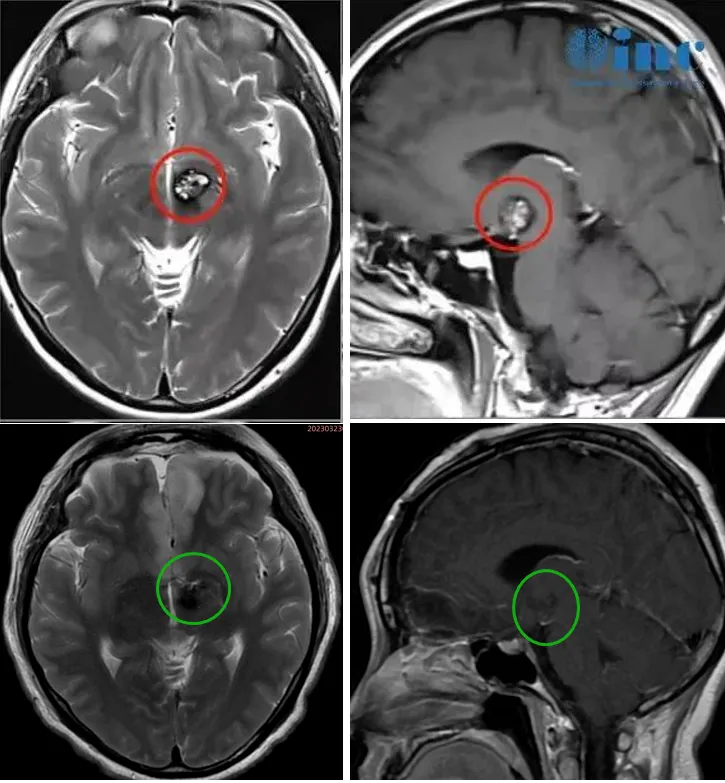

术前术后影像对比

为确保手术的精准与安全,巴特朗菲教授制定了周密的手术方案:采用额底纵裂经终板入路实施丘脑占位切除术,全程配合MEP+SEP神经电生理监测,实时监测神经功能状态。由于肿瘤位置深在,术中导航易因脑脊液释放引发漂移,巴特朗菲教授还将前联合作为关键解剖标记,精准定位肿瘤位置——它正位于前联合后方。

巴特朗菲教授凭借数十年的临床经验,在显微镜下谨慎操作,避开密集的神经与血管,逐步剥离病灶。神经电生理监测仪上的各项数据始终保持稳定,为手术过程提供保障。数小时后,手术顺利完成:病灶被完全切除,患者的神经功能也得到了完整保护。